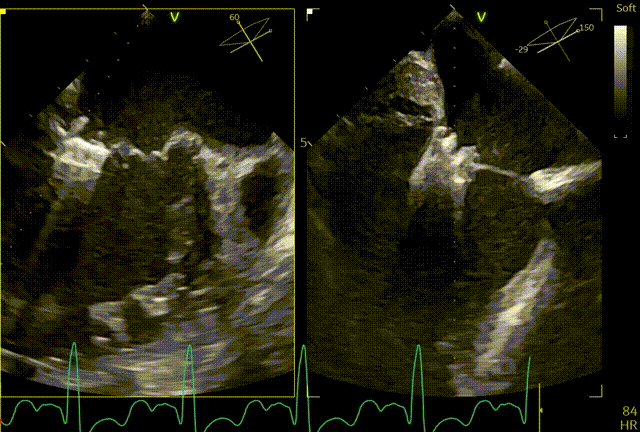

术前心超团队王蓓教授以及余婵教授对患者的瓣膜解剖情况进行了详细的评估:

① 二尖瓣后叶广泛栓系,前后叶对合不良,二尖瓣重度关闭不全,Carpentier分型Ⅲb,反流程度4+;

② 画迹法显示二尖瓣瓣口面积5.25cm²,平均跨瓣压差4.2mmHg;

③ 二尖瓣前叶(A1)长度28.5mm,二尖瓣后叶(P1)长度: 10.4mm;二尖瓣前叶(A2)长度28.4mm,二尖瓣后叶(P2)长度: 12.7mm二尖瓣前叶(A3)长度22.6mm,二尖瓣后叶(P3)长度: 11.5mm;

④ 3区前后叶对合gap 4.5mm,2区前后叶对合gap 3mm。

术前TTE

两腔心

短轴

四腔心zoom模式

反流情况